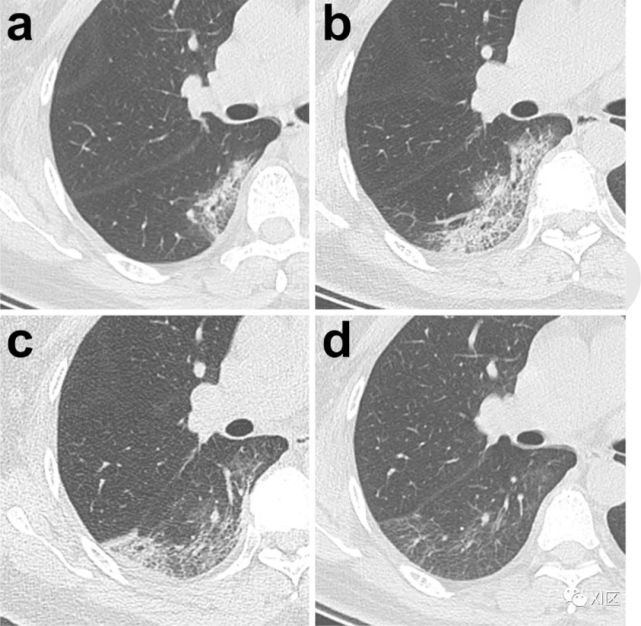

图15 27岁男性,HIV患者,高热三天。没有麻疹和免疫史。诊断为麻疹病毒肺炎。入院第11天的胸部CT图像显示双侧异常,包括小叶间隔增厚(肺尖部;B,箭)、支气管壁厚、多发大小不等的结节(分叉部;C,箭)、胸膜增厚(基底部;D,箭),以及弥漫性毛玻璃影,而第8天的胸片显示左肺出现毛玻璃影(A)。麻疹相关性肺炎的明确诊断基于三项发现:(1)体检发现;(2)微生物测试结果;和(3)典型的CT表现。

Takahashi T , Iwamoto A . Measles Pneumonia: Instructive Images by Chest Computed Tomography[J]. Journal of Experimental & Clinical Medicine, 2014, 6(2):72-73.